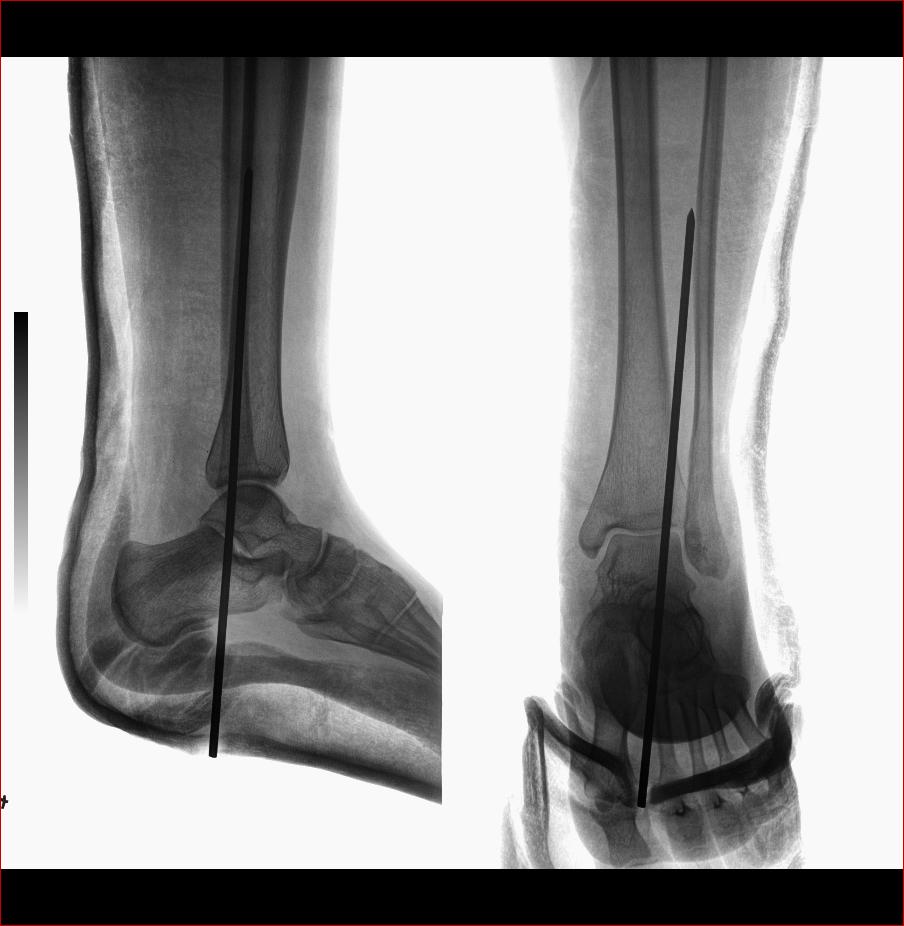

标题: X3707:跟距舟关节脱位、距骨骨折

手术所见,右跟距舟关节脱位、距骨骨折,右腓骨长、短肌、第三腓骨肌腱均断裂,胫神经挫伤。